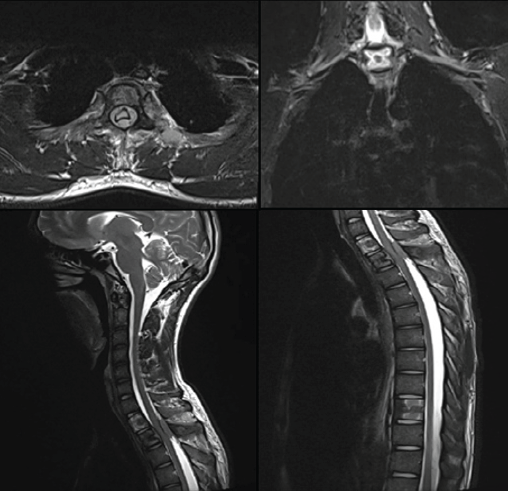

Magnetic resonance imaging (MRI) of the dorsal spine demonstrated altered marrow signal and heterogeneous post-contrast enhancement involving the D1, D2, and D10 vertebral bodies. An enhancing soft-tissue mass extended into both anterior and posterior epidural spaces at the D1–D2 level, causing severe spinal canal narrowing with cord compression and myelopathic signal changes. Extension was noted along the bilateral neural foramina and posterior elements of D1–D3 (Fig. 2). Additional short tau inversion recovery-hyperintense foci were seen in D11, D12, L1, L3, and L5 vertebrae, several of which showed mild enhancement, raising concern for multifocal metastatic deposits.

Figure 2: Pre-operative magnetic resonance imaging of the dorsal spine showing altered marrow signal and enhancing lesion involving the D1–D2 vertebral bodies with an epidural soft-tissue component causing severe spinal canal narrowing and cord compression with associated myelopathic signal changes. Additional axial and sagittal sequences demonstrate the extent of epidural involvement and compression.